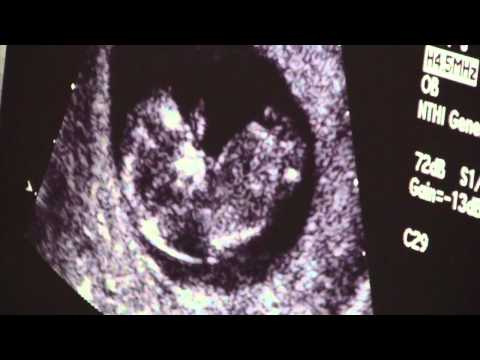

Hey everyone, I was really excited to get this on video and I thought I would share this. Especially for those who want to know somewhat what to expect at their 12 week ultrasound.

I like how you can see the heart beating and the little arms!!